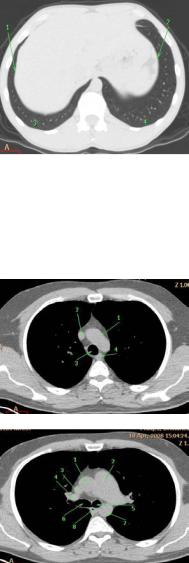

Рис. 30. КТ на уровне нижних

легочный вен в средостенном электронном окне: 1 – левый желудочек;

2 – правый желудочек;

3 – правое предсердие;

4 – левое предсердие;

5 – левая нижняя легочная вена; 6 – ветвь левой легочной

артерии; 7 – ветвь правой легочной артерии;

8 – нисходящая аорта;

9 – непарная вена;

10 – пищевод